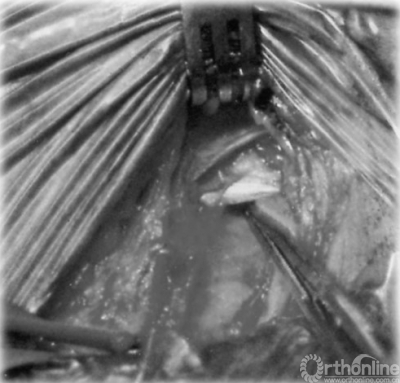

神经松解手术